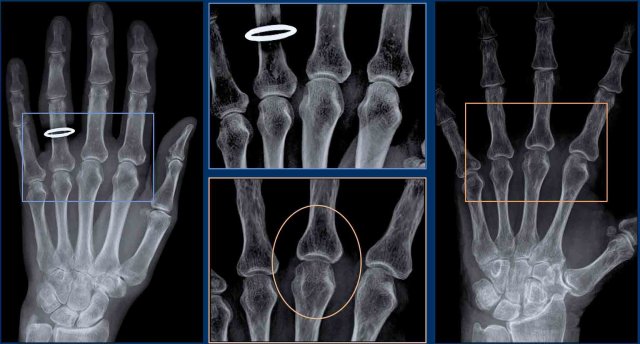

Typical examples of specific erosion patterns

1. Rheumatoid arthritis.

Typical marginal erosions in MCP-joints.

2. Erosive osteoarthritis.

Subchondral erosions in DIP- and PIP-joints. The concurrent formation of osteophytes results in a gull-wing deformity.

3. Gout.

Eccentric erosion with an overhanging edge. The sclerotic margin in this case indicates chronic and indolent disease.

4. Infection.

Destructive changes with cartilage loss and erosions.

5. Psoriatic arthritis.

Bony erosions narrowed the end of the proximal phalange as a “pencil”, which rests in the “cup” formed by the expanded base of the distal phalanx as a result of bony proliferations.

6. Scleroderma.

And other multisystem disorders can produce erosions at the distal tufts, this is called acro-osteolysis.